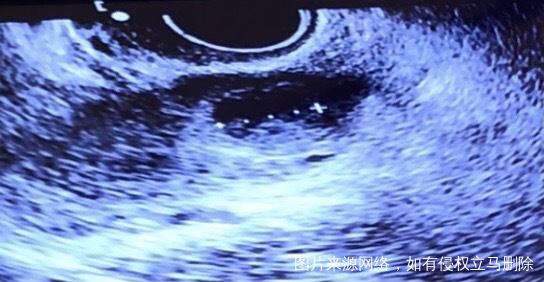

第一张图排卵前卵泡20毫米第二张图排卵后第六